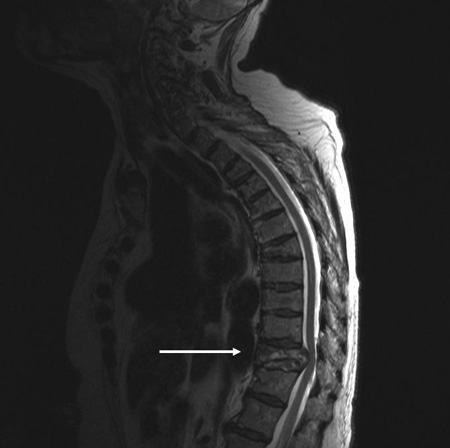

MRI thoracic spine: sagittal view (T2-weighted sequence) showing a pathologic fracture of the T10 vertebral body caused by multiple myeloma

From the personal collection of Dr B. Nurboja and Mr D. Choi